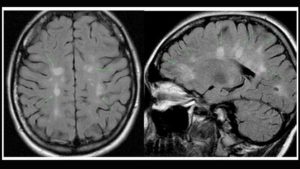

Характерное проявление рассеянного склероза на снимках – это выявление множественных мелких очагов в веществе головного и спинного мозга. Они выглядят как участки просветления на снимке.

- «Пальцы Доусона». Это демиелинизация (разрушение миелиновых волокон) белого вещества ГМ. Патологические образования имеют продолговатую форму и располагаются вдоль малых мозговых вен перпендикулярно к боковым желудочкам.

- Множественность поражений и их локализация в перивентрикулярной области.

С помощью МРТ при рассеянном склерозе выявляют распределение очагов демиелинизации в пространстве и определяют их возраст. Исследование проводят в трех плоскостях при толщине срезов 1-3мм.

Сканирование рекомендуют проводить на аппаратах с силой магнитного поля более 0.

5 Тл, сочетая исследования в аксиальной (поперечный срез) и сагиттальной плоскостях (вид сбоку) – для МРТ головного мозга.

В белом веществе спинного мозга и в глубинных отделах головного выявляют бляшки РС различного количества и размеров. Характерным является их расположение по краям мозолистого тела, в ножках, стволе, мозжечке.

В типичных случаях в структурах головного мозга в режиме Т2-взвешенных изображений выявляют очаги повышенной интенсивности овальной формы от 2 до 20 мм вдоль тел и рогов желудочков, в мозолистом теле, реже — в белом веществе полушарий головного мозга, стволе, мозжечке. Свежие очаги хорошо визуализируются при контрастировании.